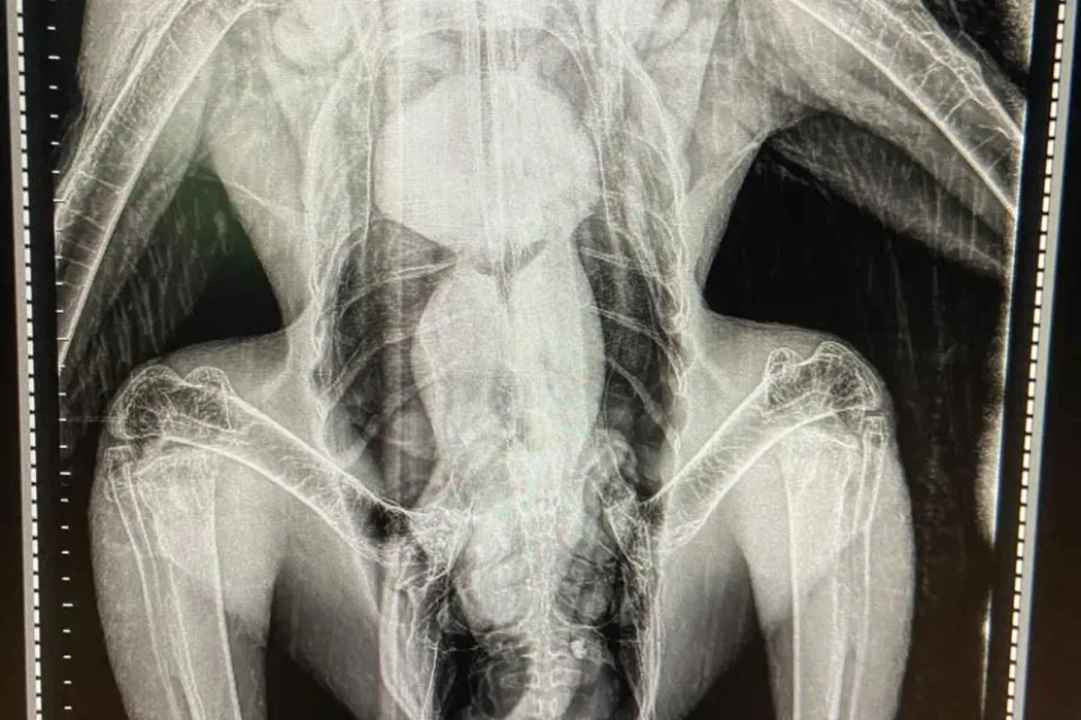

El ave fue recibida en el bioparque bonaerense, donde se le practicaron radiografías y curaciones. “Ayer recién se lo se lo pudo traer de vuelta”, precisó Lagos sobre el cierre del tratamiento y el retorno a la provincia. El operativo final incluyó el traslado desde Chos Malal y la liberación en cercanías de Huinganco.